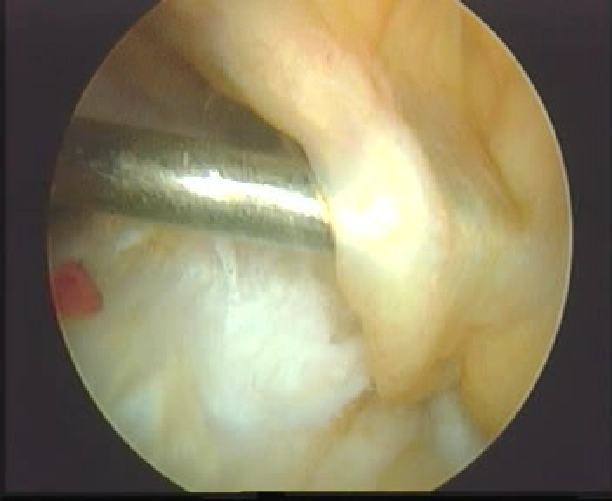

清理髁间窝

刨削切除ACL残端,以保证视野清晰以及准确定位

髁间窝狭窄者可行髁间窝成形术

拉进移植物

界面螺钉固定移植物

上胫骨端界面螺钉

拉紧B-P-B,并行后抽屉试验,紧张重建韧带,上胫骨端的界面螺钉,必要时可用门型钉或普通螺丝钉加强固定。

用探钩检查,重建韧带张力良好,前抽屉试验阴性,膝关节屈伸正常。